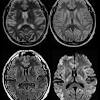

Il existe une spongiose disséminée à l'intérieur du cortex cérébral. Description affection très rare et fatale qui attaque le système nerveux 2 types de mcj : A chaque âge correspondent des conditions de vie et des préoccupations différentes.

L'encéphalopathie spongiforme bovine (la rage des vaches) est considérée comme une variante de la mcj.